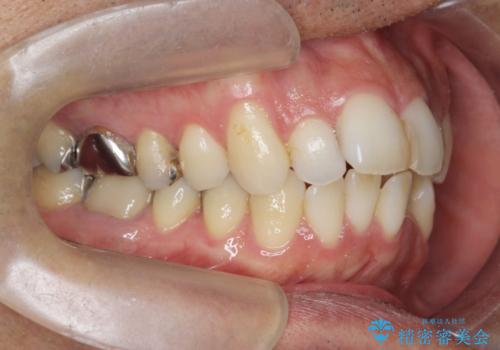

- 突き出た前歯の角度の改善と虫歯治療の改善を求めて来院されました。

虫歯を除去したのち、マウスピース矯正治療を行い、歯並びやがたつきを改善したのち、セラミックに置き換えることで審美性の向上を計画します。